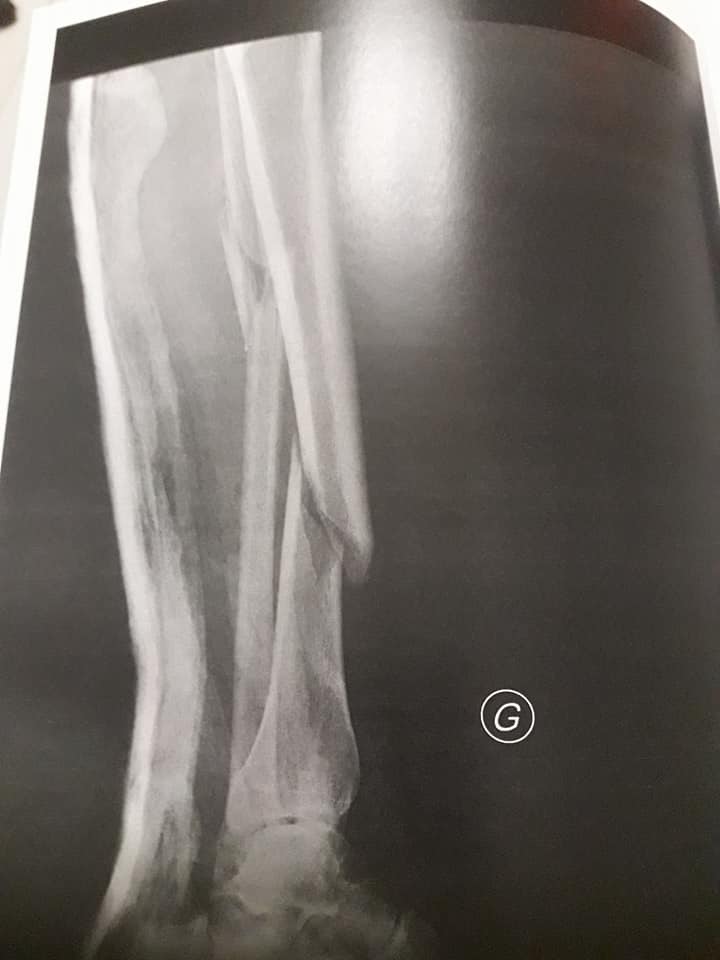

G.B. est un miraculé de la montagne. En effet samedi 20 janvier alors qu’il chasse le chamois , il fait une mauvaise chute sur la commune de Seythenex.

Il explique en exclusivité sa mésaventure : De retour de chasse aux chamois samedi, j’ai perdu l’équilibre au-dessus d’une barre rocheuse et je suis tombé. Et je suis même très mal tombé dans cette chute.